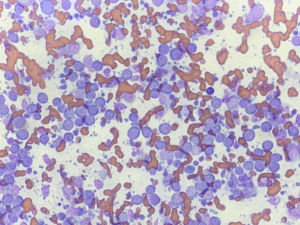

犬の口腔内メラノーマ(悪性黒色腫)

犬の口腔内メラノーマは、特に高齢犬や小型犬に多く発生する悪性腫瘍です。歯肉、舌、頬粘膜、口唇などにでき、外見は黒く見えることが多いものの、色がないタイプ(無色素性)も存在します。転移率が高く(リンパ節転移 58-74%、 […]